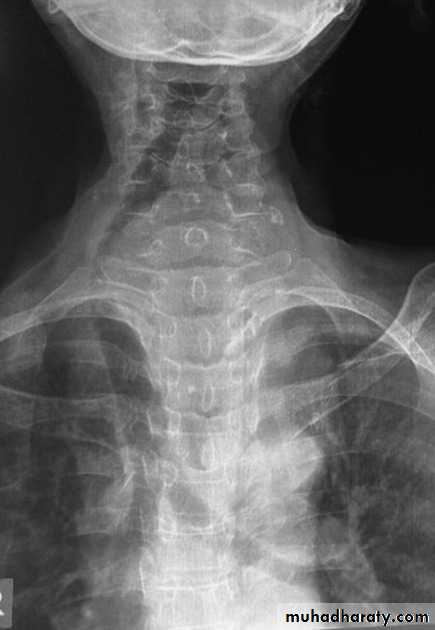

Retro sternal goiter

Radiographic featuresChest radiograph

It may show a superior mediastinal radio-opacity causing the deviation of trachea to opposite site. The superior margin of the radio-opacity/mass is untraceable (cervicothoracic sign).